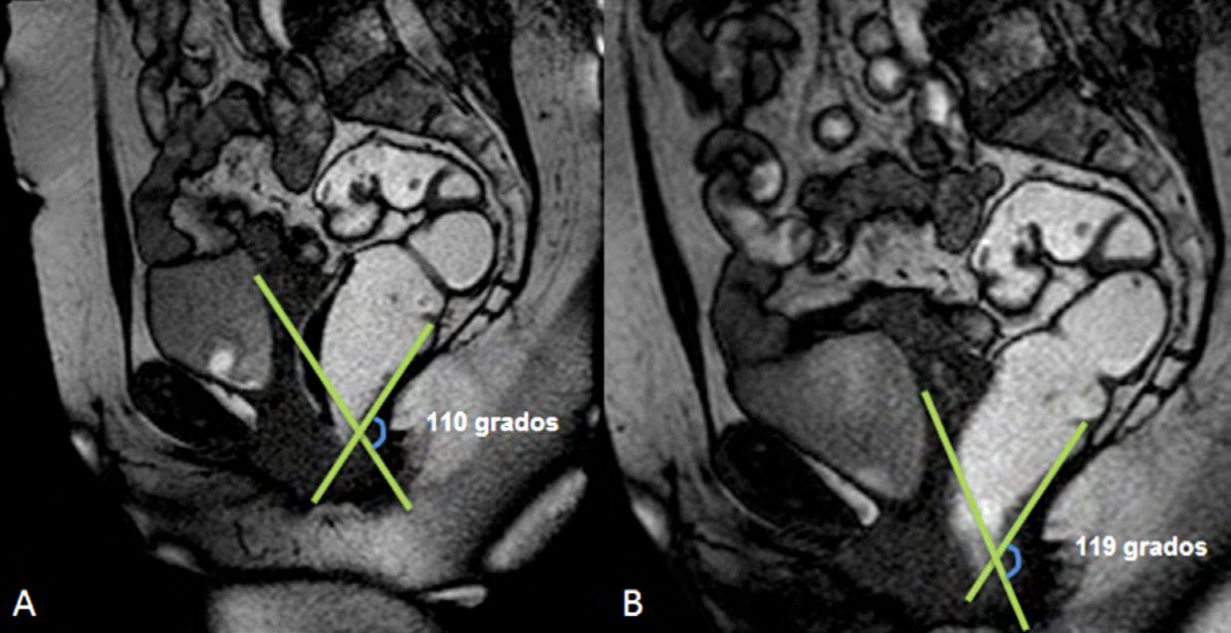

Figura 3

Ángulos de referencia. Medición del ángulo ano-rectal en una paciente sin patología del piso pélvico. Imagen de la línea media potenciada en T2 en el plano sagital. Durante el reposo el ángulo ano-rectal debe ser entre 108 y 127°. Durante la defecación el ángulo se vuelve más obtuso con una variación de hasta más 20° con respecto al reposo.

La línea M es perpendicular a la PCL a nivel del sector más posterior de la línea H y representa el descenso del hiato del elevador, con un valor normal menor a 2 cm. El ángulo ano rectal es el ángulo entre el eje central del canal anal y la pared posterior del recto, con un valor normal entre 108º y 127º y una variación de hasta 15º en Valsalva.